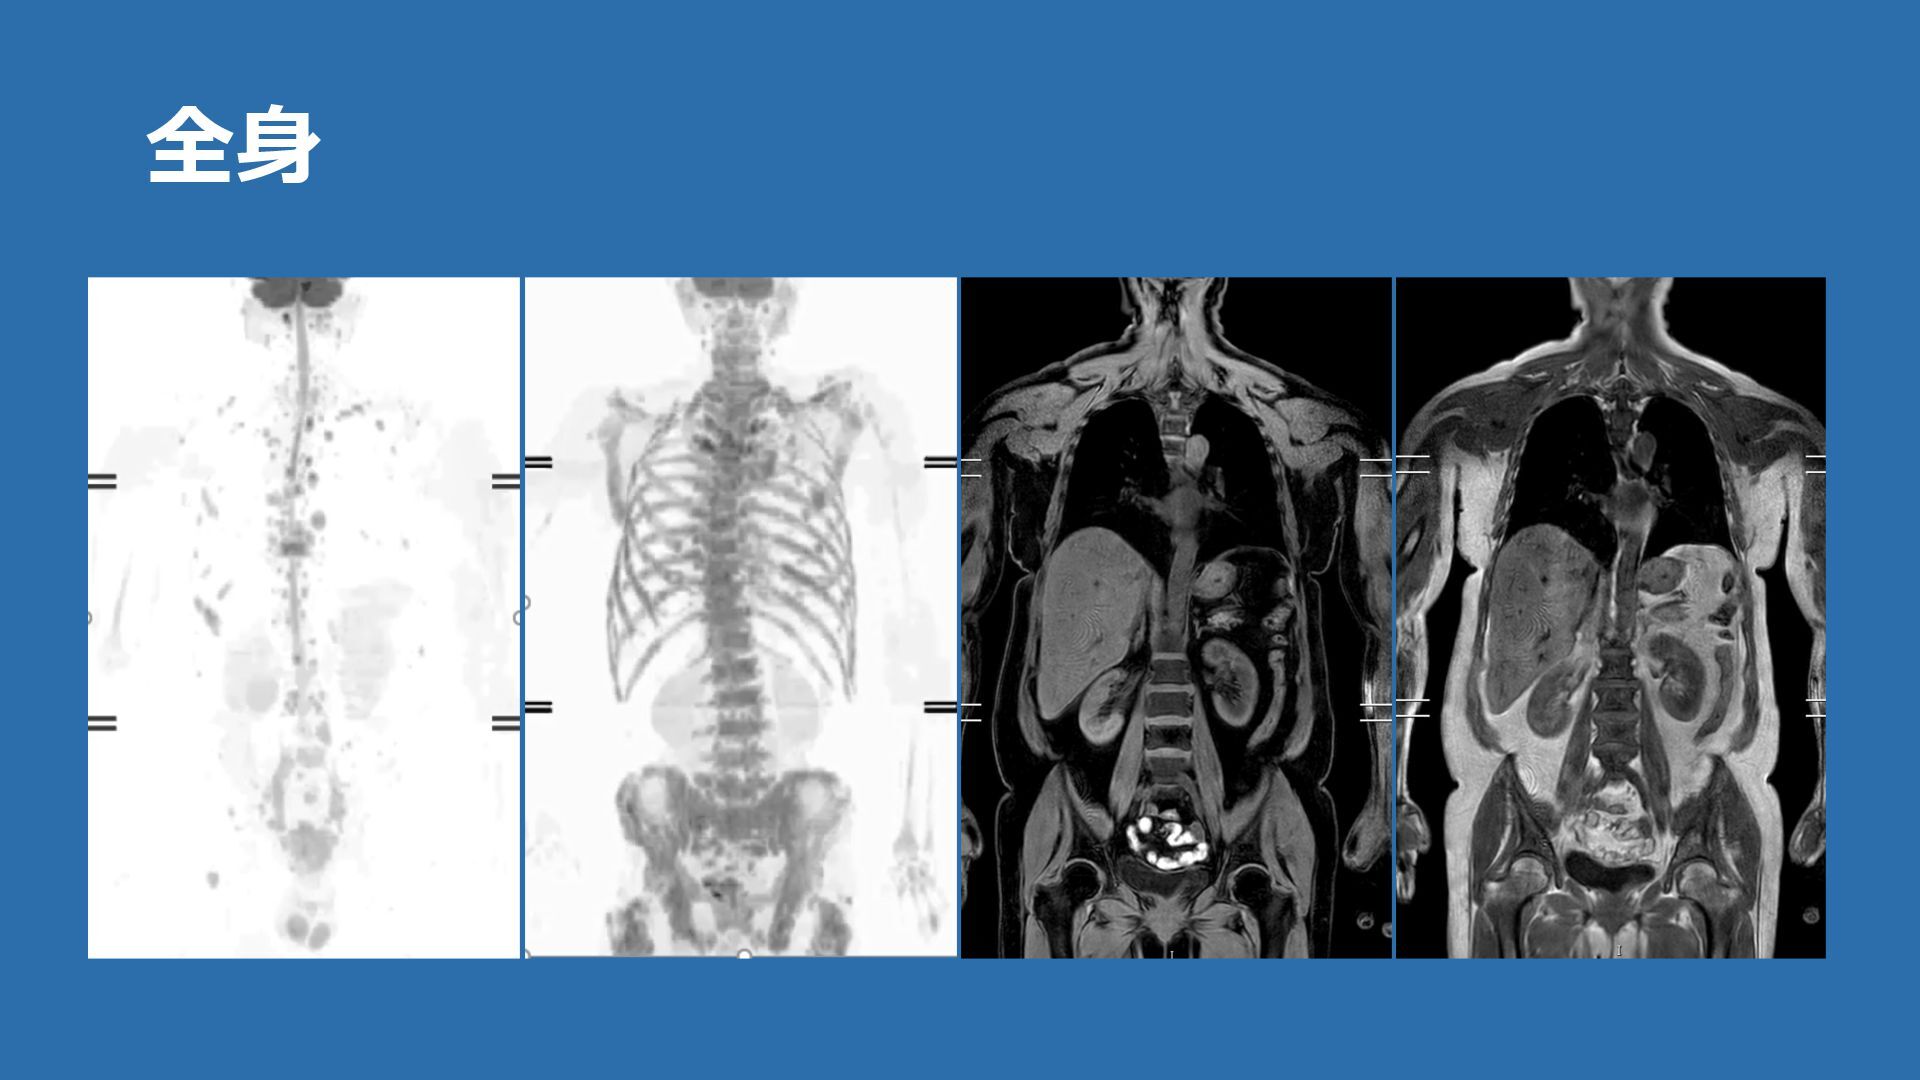

全⾝